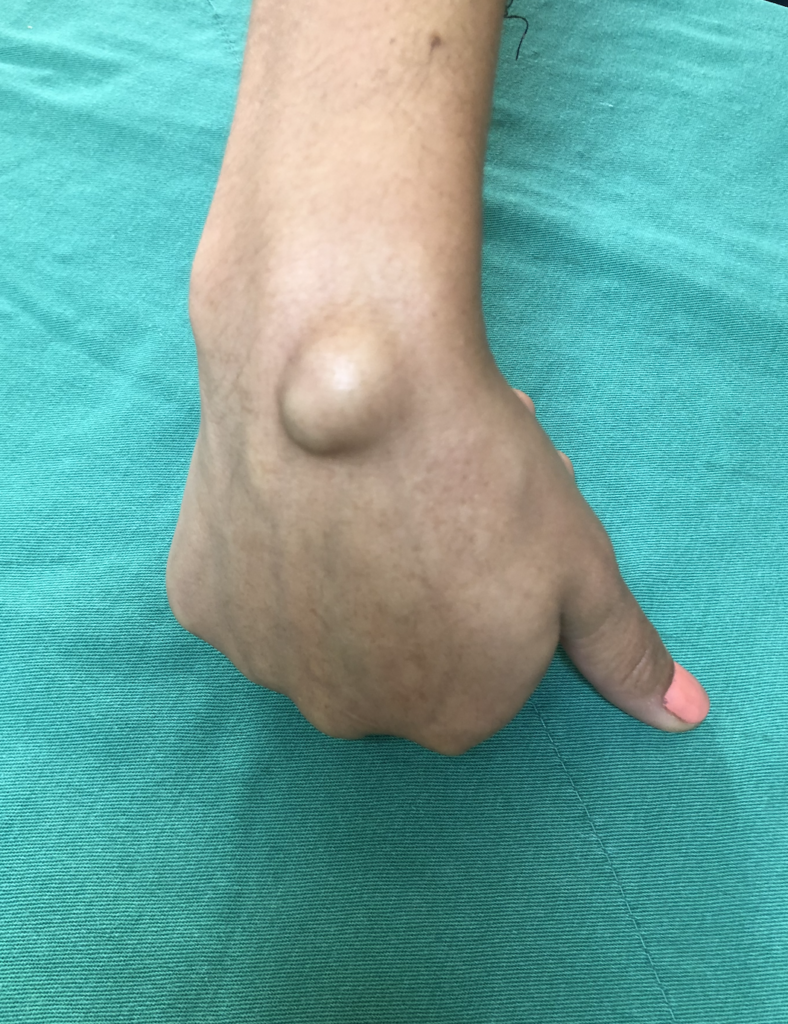

O cisto artrossinovial no punho é uma das principais causas de “caroço” na mão e motivo frequente de consulta com cirurgião de mão em São Paulo, especialmente na região do Itaim Bibi.

O cisto artrossinovial, também chamado de cisto sinovial, é uma lesão benigna formada por líquido viscoso, proveniente da articulação ou da bainha dos tendões.

- No dorso do punho (mais comum)

Apesar de benigno, pode causar dor, limitação e impacto estético.

- Caroço visível no punho